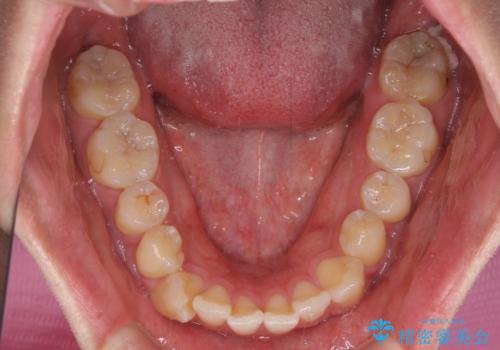

八重歯と前歯のクロスバイト ワイヤー装置で短期間矯正

上顎側切歯(前から2番目の歯)が内側に転位している歯列は、インビザラインでは排列が困難であることが多いため、期間を短く、より良い仕上がりとするため、ワイヤー装置にて矯正治療を行うこととしました。